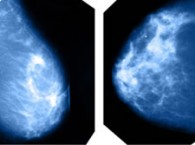

Ibermática promotes an “artificial intelligence” project to help prevent and diagnose breast cancer

Ibermática, through its Institute for Innovation, i3B, has begun an “artificial intelligence” project whose goal is to achieve an early... -